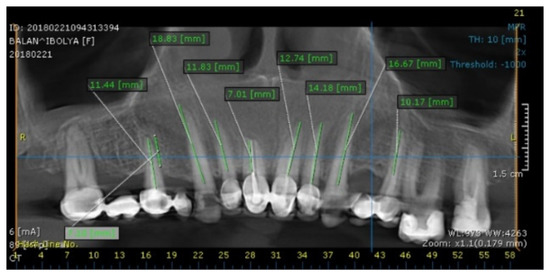

2. Case Report